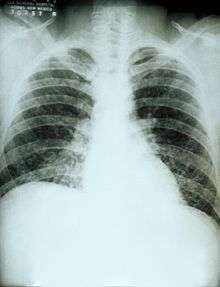

If symptoms of histoplasmosis infection occur, they will start within 3 to 17 days after exposure; the average is 12–14 days. Most affected individuals have clinically silent manifestations and show no apparent ill effects.[4] The acute phase of histoplasmosis is characterized by non-specific respiratory symptoms, often cough or flu-like. Chest X-ray findings are normal in 40–70% of cases.[4] Chronic histoplasmosis cases can resemble tuberculosis;[5][6] disseminated histoplasmosis affects multiple organ systems and is fatal unless treated.[7]